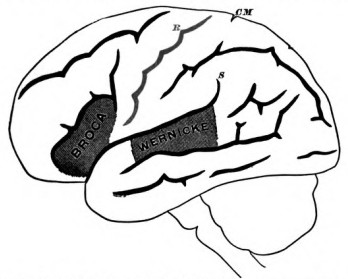

Phrenology hardly does more than restate the problem. To answer the question, "Why do I like children?" by saying, "Because you have a large organ of philoprogenitiveness," but renames the phenomenon to be explained. What is my philoprogenitiveness? Of what mental elements does it consist? And how can a part of the brain be its organ? A science of the mind must reduce such complex manifestations as 'philoprogenitiveness' to their elements. A science of the brain must point out the functions of its elements. A science of the relations of mind and brain must show how the elementary ingredients of the former correspond to the elementary functions of the latter. But phrenology, except by occasional coincidence, takes no account of elements at all. Its 'faculties,' as a rule, are fully equipped persons in a particular mental attitude. Take, for example, the 'faculty' of language. It involves[Pg 29] in reality a host of distinct powers. We must first have images of concrete things and ideas of abstract qualities and relations; we must next have the memory of words and then the capacity so to associate each idea or image with a particular word that, when the word is heard, the idea shall forthwith enter our mind. We must conversely, as soon as the idea arises in our mind, associate with it a mental image of the word, and by means of this image we must innervate our articulatory apparatus so as to reproduce the word as physical sound. To read or to write a language other elements still must be introduced. But it is plain that the faculty of spoken language alone is so complicated as to call into play almost all the elementary powers which the mind possesses, memory, imagination, association, judgment, and volition. A portion of the brain competent to be the adequate seat of such a faculty would needs be an entire brain in miniature,—just as the faculty itself is really a specification of the entire man, a sort of homunculus.

Modern Science conceives of the matter in a very different way. Brain and mind alike consist of simple elements, sensory and motor. "All nervous centres," says Dr. Hughlings Jackson,[9] "from the lowest to the very highest (the[Pg 30] substrata of consciousness), are made up of nothing else than nervous arrangements, representing impressions and movements.... I do not see of what other materials the brain can be made." Meynert represents the matter similarly when he calls the cortex of the hemispheres the surface of projection for every muscle and every sensitive point of the body. The muscles and the sensitive points are represented each by a cortical point, and the brain is nothing but the sum of all these cortical points, to which, on the mental side, as many ideas correspond. Ideas of sensation, ideas of motion are, on the other hand, the elementary factors out of which the mind is built up by the associationists in psychology. There is a complete parallelism between the two analyses, the same diagram of little dots, circles, or triangles joined by lines symbolizes equally well the cerebral and mental processes: the dots stand for cells or ideas, the lines for fibres or associations. We shall have later to criticise this analysis so far as it relates to the mind; but there is no doubt that it is a most convenient, and has been a most useful, hypothesis, formulating the facts in an extremely natural way.

If, then, we grant that motor and sensory ideas variously associated are the materials of the mind, all we need do to get a complete diagram of the mind's and the brain's relations should be to ascertain which sensory idea corresponds to which sensational surface of projection, and which motor idea to which muscular surface of projection. The associations would then correspond to the fibrous connections between the various surfaces. This distinct cerebral localization of the various elementary sorts of idea has been treated as a 'postulate' by many physiologists (e.g. Munk); and the most stirring controversy in nerve-physiology which the present generation has seen has been the localization-question.

Up to 1870, the opinion which prevailed was that which the experiments of Flourens on pigeons' brains had made plausible, namely, that the different functions of the hemispheres[Pg 31] were not locally separated, but carried on each by the aid of the whole organ. Hitzig in 1870 showed, however, that in a dog's brain highly specialized movements could be produced by electric irritation of determinate regions of the cortex; and Ferrier and Munk, half a dozen years later, seemed to prove, either by irritations or excisions or both, that there were equally determinate regions connected with the senses of sight, touch, hearing, and smell. Munk's special sensorial localizations, however, disagreed with Ferrier's; and Goltz, from his extirpation-experiments, came to a conclusion adverse to strict localization of any kind. The controversy is not yet over. I will not pretend to say anything more of it historically, but give a brief account of the condition in which matters at present stand.